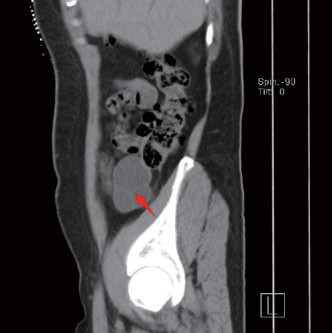

妇科超声:子宫大小 105×107×75mm,边界欠清,子宫壁见多个大小不等实性占位:考虑多发子宫肌瘤。左附件区一 64×45×93mm 实性团块,内见丰富血流信号:颗粒细胞瘤?下腹部 CT(如图 1-3):左附件区见团片状软组织密度影,边界清楚,大小约 5.7×6.6×10.7cm,周围脂肪间隙模糊,邻近腹膜稍增厚,见散在稍大淋巴结影(如图 1-3)。E2、肿瘤标志物(CA199、CA125、HE4)、胸部 CT、上中腹部 CT 等常规检查均无异常。 图 2

CT 表现 :病灶轮廓清楚,密度均匀。